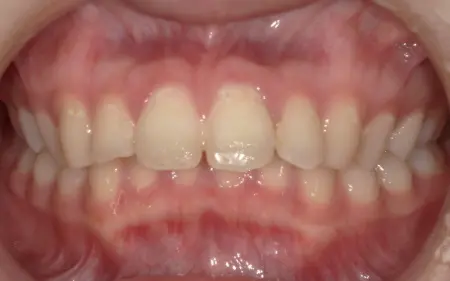

2025.11.0920代女性 マルチブラケット装置やヘッドギアを併用した矯正治療で出っ歯を改善した症例